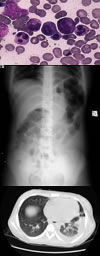

貓泛白細胞減少症是一種主要侵害幼貓的高度接觸性傳染病。潛伏期2~9天,平均4天。本病的臨床表現甚為多樣,分為特急性型、急性型、亞急性型和不顯型。特急性型不待發現臨床症狀即突然死亡,畜主往往懷疑為中毒。急性型可於24小時內死亡。亞急性型可持續數日到一周,呈雙相熱。第一期發熱時病畜體溫升高40℃左右,持續約一天,發熱平息後數天第二次發熱,體溫40℃以上,同時出現厭食、嘔吐、沉鬱、出血性腸炎和脫水等症狀,病貓多於5~6天死亡,死亡率一般為60%~70%。

人工感染時,多種途徑(經口、鼻、皮下、靜脈、腹腔等)均能引起貓發病,尤其幼齡動物更為敏感。在體溫開始升高前不久,出現短時間的白細胞增多。第二次發熱後,白細胞嚴重減少,甚至在血液塗片標本上難以找到白細胞,故名貓泛白細胞減少症。正常貓血清中白細胞數為15000~20000個/mm3。白細胞數減少到8000個/mm3左右時,即可懷疑為本病,5000個/mm3以下時表示重症。2000個/mm3以下預後不良,以淋巴細胞和中性多核白細胞減少為主。

由於病毒對處於有絲分裂過程中的細胞有選擇親和性,所以大多數病變都發生在旺盛增殖的組織,如骨髓的幹細胞、淋巴細胞生成組織和腸黏膜。病毒對新生貓小腦內旺盛增殖的生髮細胞,具有選擇親和性,致使病貓發生共濟失調。當感染髮生於妊娠後期時,病毒能通過胎盤屏障,引起胎兒小腦發育不全、死亡和流產。

除特急性病貓外,剖檢可見脫水和消瘦變化。空腸和迴腸局部充血,脾腫大,腸系膜淋巴結水腫、壞死。多數病例長骨的紅髓變為液狀或半液狀,此點具有一定的診斷價值。組織學檢查時,於腸管上皮細胞可見嗜酸和嗜鹼性兩種包涵體,但病程超過3~4天以上者,往往消失。

根據臨床症狀、病理組織學變化(骨髓呈液狀、半液狀,小腸黏膜上皮細胞核內的包涵體)和白細胞減少等,可作出初步診斷。確診要靠病毒分離或免疫血清學試驗。